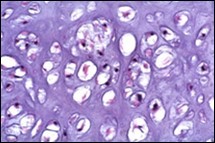

Characteristically, enchondroma is below < 5 centimetre magnitude although enlarged lesions can be considered benign when accompanying indeterminate or atypical microscopic features are absent4, 5. Enchondroma is composed of well-circumscribed nodules of benign hyaline cartilage. Incorporated chondrocytes demonstrate miniature, uniform, spherical nuclei with condensed chromatin. Bi-nucleate cells are infrequent4, 5.

Typically, chondroid matrix of an enchondroma depicts foci of punctate calcification. Tumour cell nuclei are fairly uniform. Mitotic figures are few. Extensively calcified enchondromas are associated with foci of endochondral ossification 4, 5.

The neoplasm is configured of lobules of hyaline cartilage enveloped by perichondrium-encased bone. Tumefaction can be hyper-cellular with bi-nucleate tumour cells. Myxoid change, foci of calcification and endochondral ossification are discerned. Necrosis may ensue on account of avascular cartilaginous component. Tongues of bone appear to extend into subjacent cartilage demonstrating a sharply defined interface confined to the growth plate4, 5.

Figure 4.Enchondroma depicting lobules of hyaline cartilage with vacuolated cells and eccentric nuclei 12.

Figure 5.Enchondroma enunciating lobules of uniform cartilaginous cells with regular, centric nuclei and absence of mitosis 13.

Figure 6.Enchondroma exemplifying lobules of hyaline cartilage composed of enlarged, vacuolated cells with uniform nuclei. Focal calcification is absent 14

Figure 7.Enchondroma enunciating lobular hyaline cartilage with constituent vacuolated chondrocytes an uniform nuclei 15.

Figure 8.Enchondroma delineating hyaline cartilaginous cells with vacuolated cytoplasm and uniform nuclei 16.